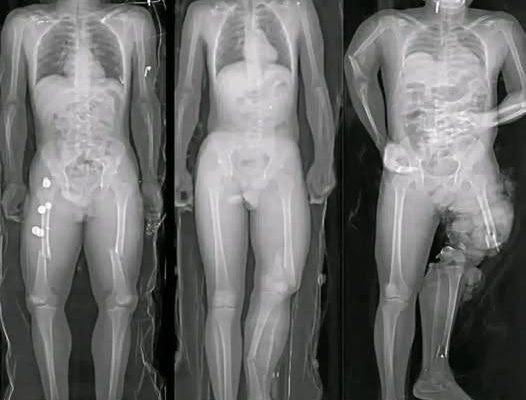

In recent months, a wave of alarming images and short messages has circulated widely across social media platforms, often accompanied by phrases such as “If you got the COVID vaccine, you should know this.” Many of these posts feature dramatic visuals—most notably illustrations of syringes aimed directly at the human heart—designed to provoke fear and urgency. While the images are striking, they rarely provide verified medical context. Instead, they rely on emotional reaction rather than evidence.

The success of these viral messages lies in how they are constructed. Fear-based imagery has always been effective at capturing attention, especially when combined with incomplete or vague warnings. A syringe aimed at a heart immediately suggests danger, even before a viewer reads any accompanying text. This technique taps into a natural instinct to protect oneself from harm.